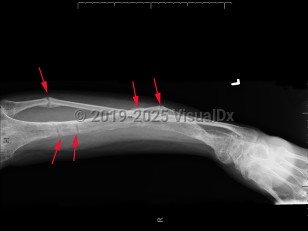

Imaging Studies image of Familial hypophosphatemic rickets - imageId=7907912. Click to open in gallery.  caption: '<span>Severe osteopenia (with a  blurry lucent/sclerotic appearance), with multiple looser zones involving  the tibia, resulting in lateral bowing and a healing fracture of the  proximal fibula. Findings are compatible with the clinical history of  hypophosphatemic rickets.</span>'

Severe osteopenia (with a blurry lucent/sclerotic appearance), with multiple looser zones involving the tibia, resulting in lateral bowing and a healing fracture of the proximal fibula. Findings are compatible with the clinical history of hypophosphatemic rickets.